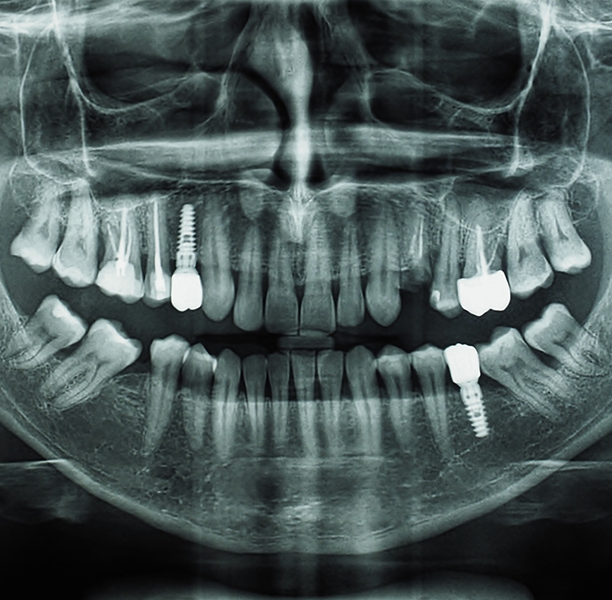

Much of our dental office is centered around restoring dental implants. If you are working on a restorative case that is particularly extensive or complex, we would be happy to consult with you. Dr. Lamberti will use his skills as a restorative and cosmetic dentist in Boca Raton to help your patient experience the life-changing benefits of high-quality replacement teeth.

For example, if Dr. Lamberti is designing a crown for a dental implant, he does more than make sure the crown fits in well with the teeth that are adjacent to it. He also considers the position of the opposing tooth (or teeth). If the opposing tooth has shifted out of its anatomically correct position, an interference results, and bite forces are incorrect. This affects both the crown’s long-term viability and the patient’s biting function capability.